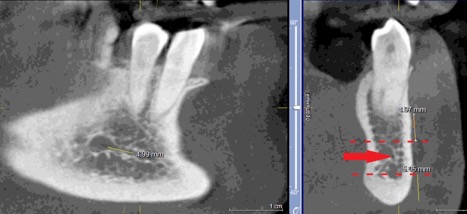

При измерении расстояния от резцовой петли до вестибулярной стенки нижней челюсти и её топографии в области правила «трёх пятёрок», выделено три положения канала, в котором проходит резцовая петля: канал прилежит, т.е. стенка канала образована кортикальной частью (рис 3), касается, т.е. имеет одну общую точку (рис 4) и не имеет общих точек.

Рисунок 4. КЛКТ Сагиттальный и коронарный реформаты переднего отдела нижней челюсти.

Канал соприкасается с кортикальной частью кости (красная стрелка – резцовая петля).